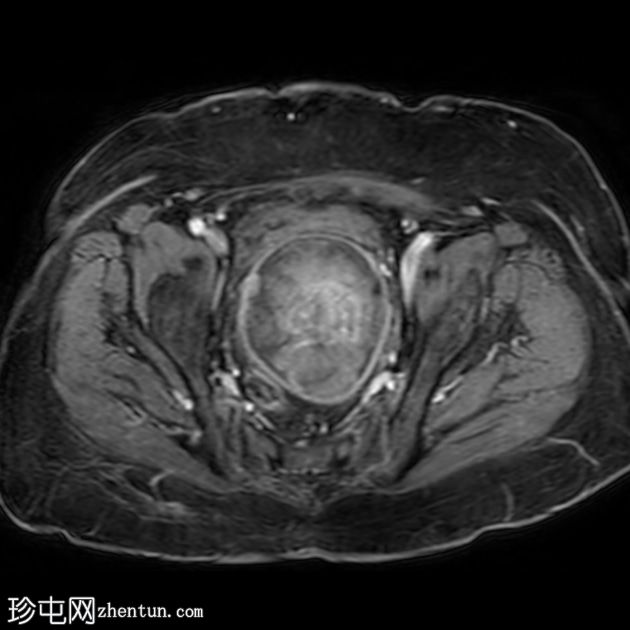

轴位

ADC

子宫呈U形,宫底轮廓消失,宫底突出至扩张的阴道内,宫颈位于内翻的宫底上方(II级子宫内翻):

宫底处可见阴道内可见边界不清、分叶状实性肿块,明显扩张阴道壁,阴道壁完整。

肿块最大轴向及头尾径约为 9.7 x 9.6 x 9.5 cm,T1 加权像呈低信号,T2 加权像呈中/高信号,伴有扩散受限和不均匀增强。

肿块前方压迫膀胱,后方紧邻乙状结肠,未见侵犯。

肿块压迫左侧远端输尿管,导致轻度输尿管肾积水。

轴位MRI:可能显示靶环状或同心环状结构,提示子宫内膜存在不同层次。